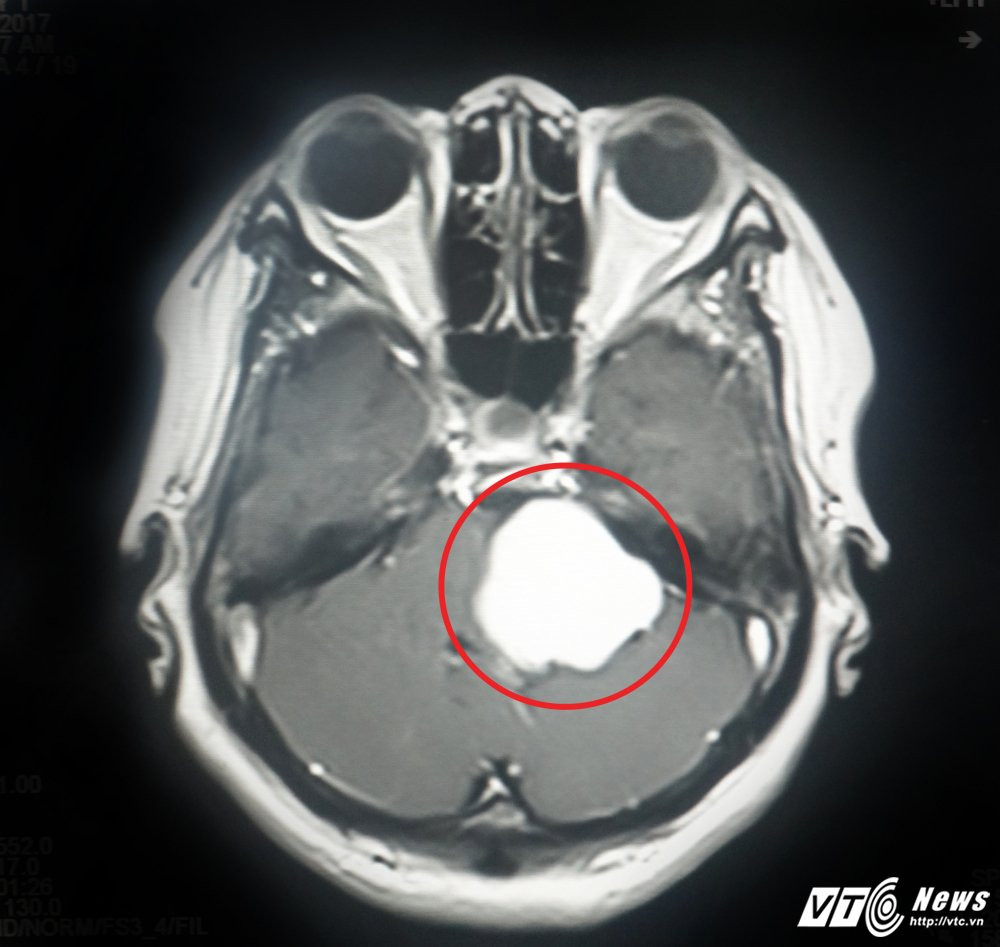

Ngày 27/10, đại diện bệnh viện Xuyên Á (TP.HCM) cho biết, đơn vị vừa phẫu thuật thành công ca tách khối u màng não to như quả bóng bàn ra khỏi mạch máu thần kinh của nam bệnh nhân.

Khối u màng não to như quả bóng bàn ra khỏi mạch máu thần kinh của nam bệnh nhân.

Tiếp nhận ca bệnh, các bác sĩ chuyên khoa Ngoại Thần kinh, bệnh viện Xuyên Á chẩn đoán xác định bệnh nhân có khối u não nằm rất sâu, ở vị trí liên quan tới nhiều dây thần kinh sọ não, và vùng chức năng quan trọng của não nơi điều hành nhịp tim và hô hấp.